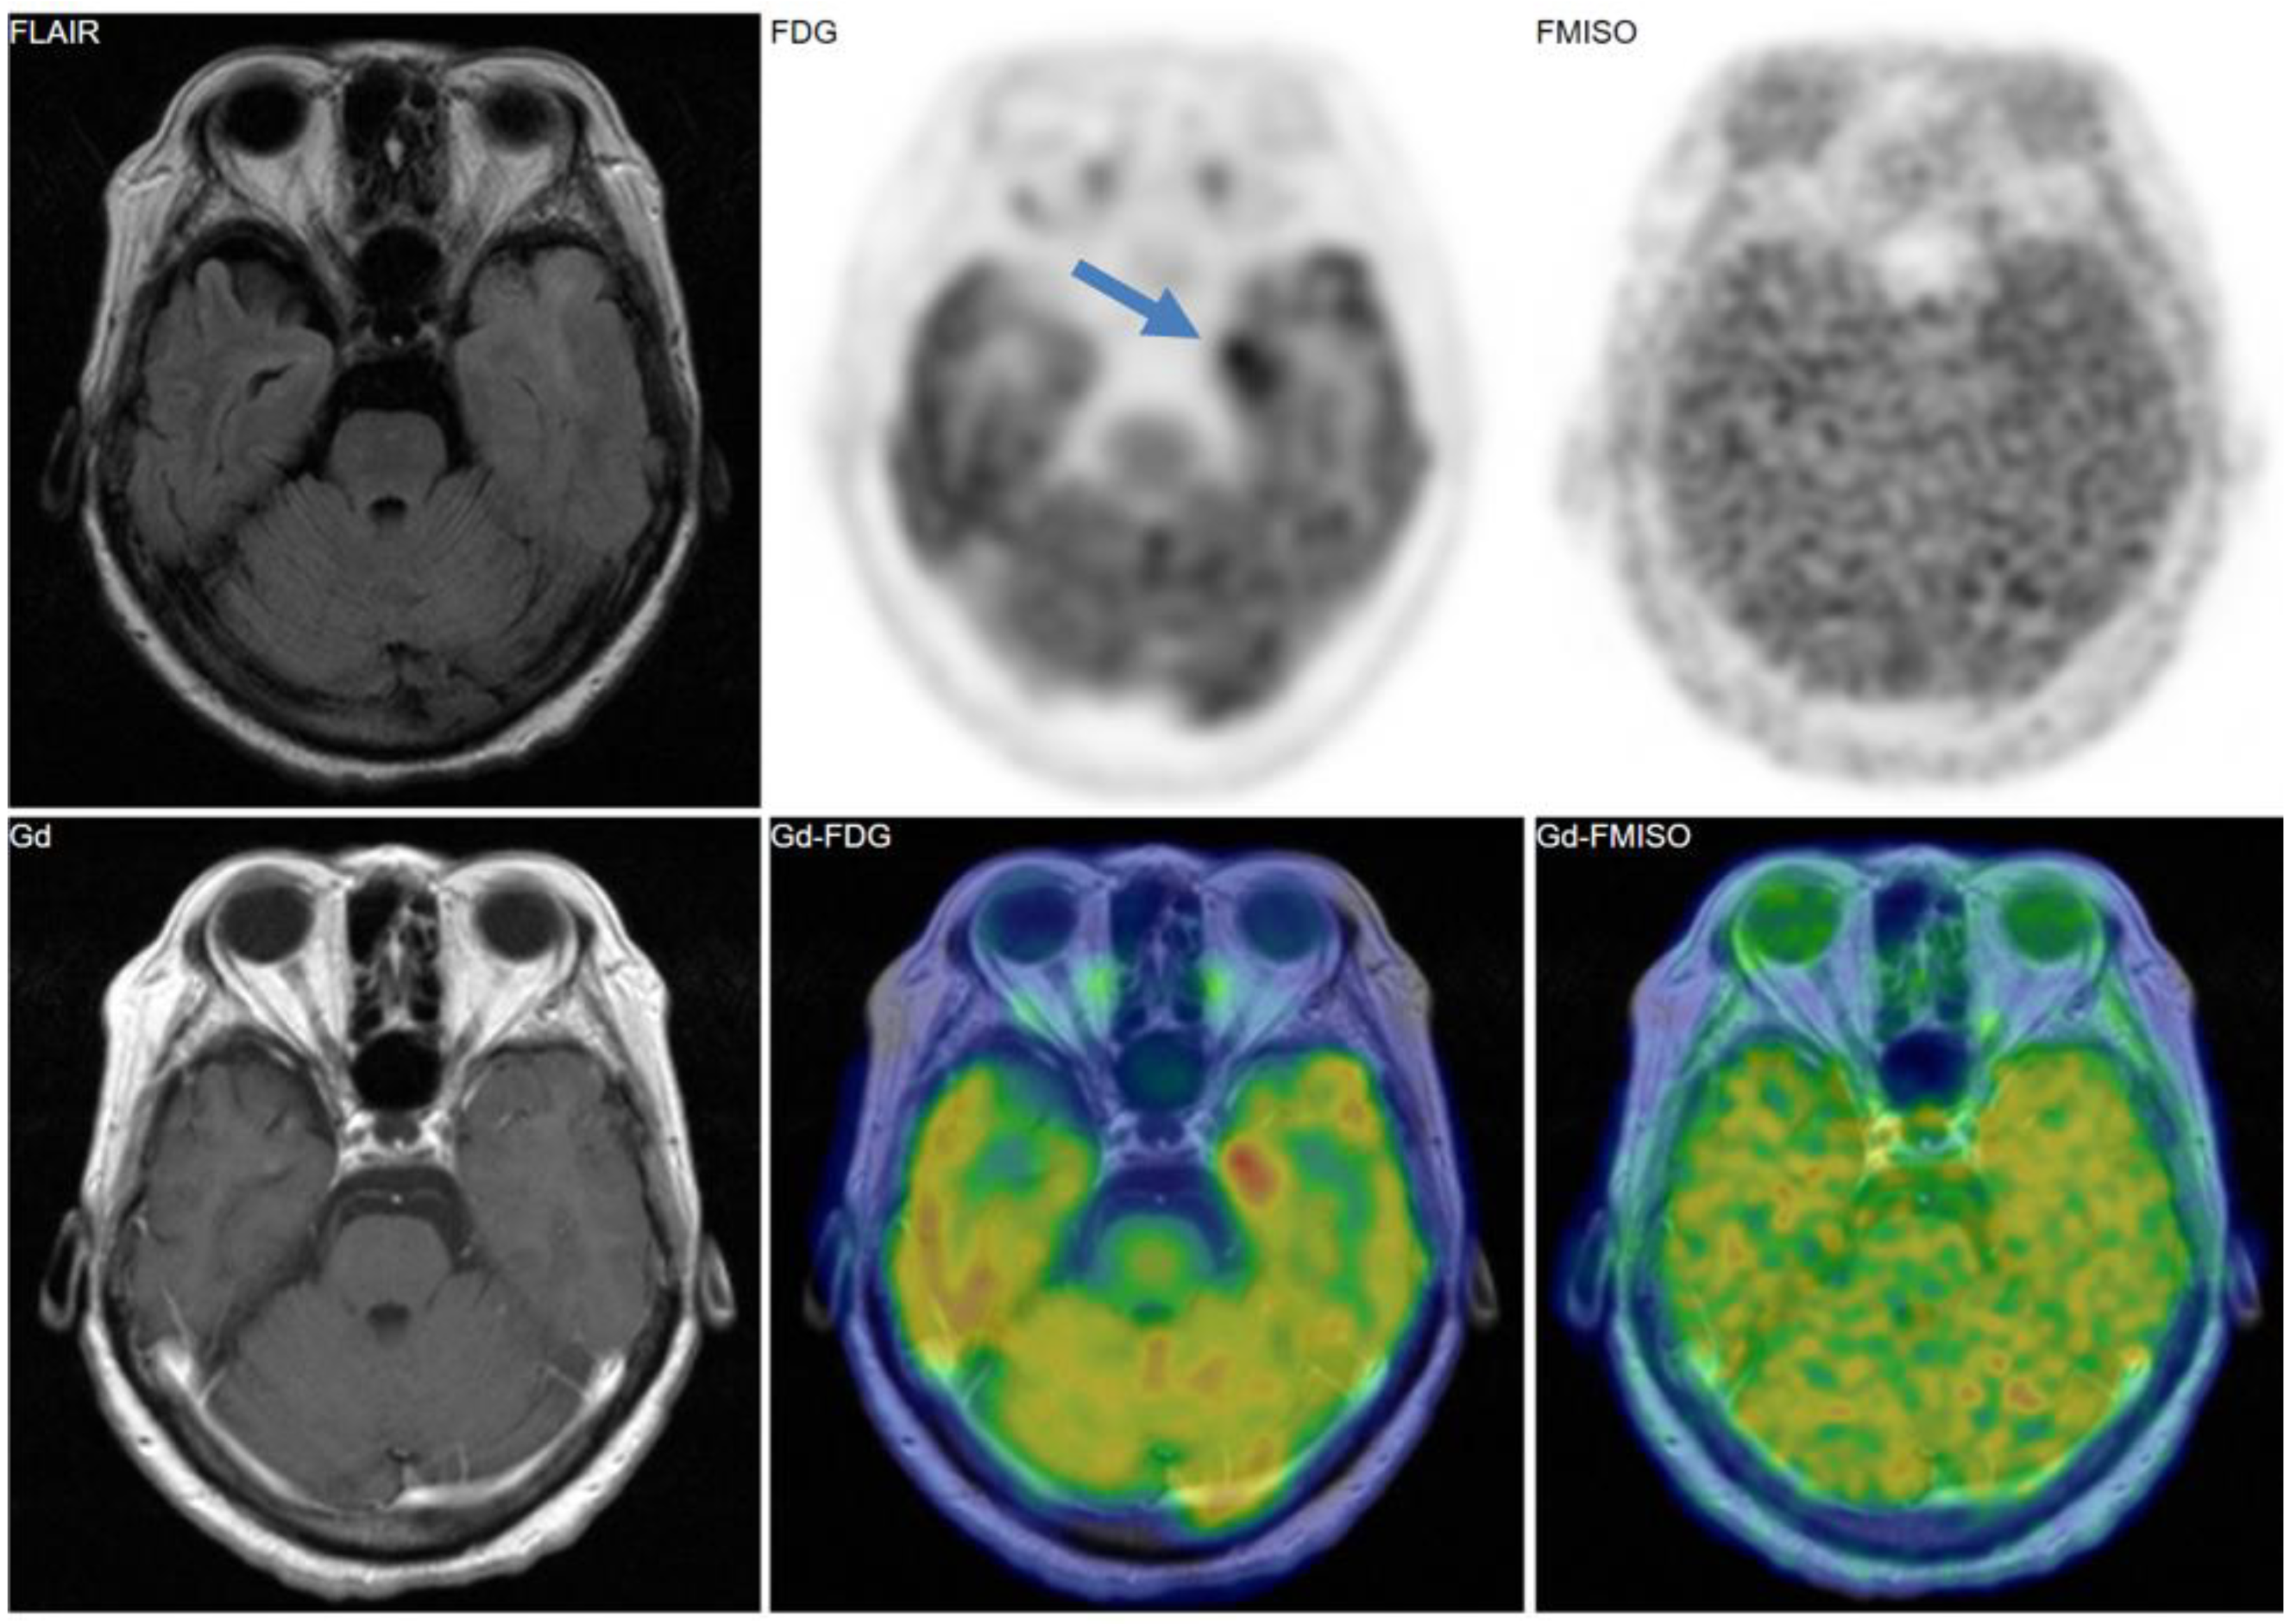

Figure 2, Figure 3 and Figure 4 show some representative cases of low to high grade gliomas. We demonstrated that FMISO has the potential to distinguish glioblastomas (i.e., grade IV gliomas) from less-malignant gliomas (i.e., grade III or lower grade gliomas) [40]. As mentioned above, the oxygen concentration threshold of FMISO uptake is low. Thus, FMISO PET can differentiate tissues with severe hypoxia from those without. Studies using direct needle electrodes suggested that the hypoxic condition of a glioma depends on its degree of malignancy [41,42,43]. We used FMISO PET and FDG PET for the preoperative examination of 23 patients with gliomas of different World Health Organization (WHO) grades [40]. The PET findings were compared with the patients’ post-operative histological findings by neuropathologists. We observed FMISO uptake in the glioblastomas, but not in the less-malignant gliomas (Table 1). In the WHO definition, glioblastoma presents with necrosis in the tumor, whereas lower-grade gliomas do not develop necrosis [44]. It is thus reasonable that only glioblastomas have severe hypoxia (beyond the FMISO threshold) and therefore take up FMISO. We concluded that FMISO PET may be able to clearly distinguish glioblastomas from lower-grade gliomas.

Figure 2. A 69-year-old patient had a tumor in the left temporal lobe. Fluid-attenuated inversion recovery (FLAIR) image showed high intensity, indicating the tumor and the peritumoral edema. Gadolinium enhancement, 18F-fluorodeoxyglucose (FDG) uptake, and FMISO uptake were observed in the same area. The pathological diagnosis was glioblastoma (grade IV).